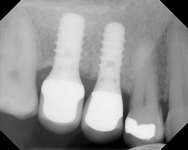

Figure 2A Antrostomy performed using piezoelectric surgery, leaving an intact sinus membrane. Figure 2B Particulate bone graft was placed to lift sinus floor.

Figure 2C Radiographic confirmation of graft localization to the desired site before membrane application and wound closure.